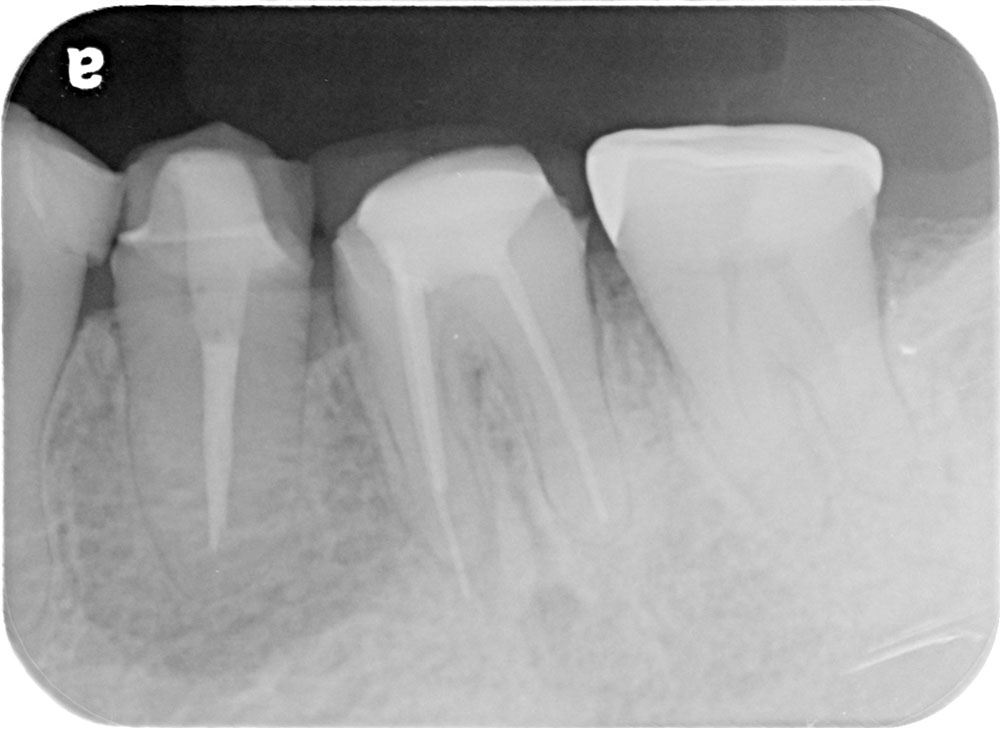

術前

術後

世代・性別

40代女性

主訴

ずっと痛い、噛むと特に痛い、前医でもうこれ以上はできないと言われた

治療内容

根管治療

治療期間

2ヶ月

治療費

保険適応内

治療のリスク

治療中または治療後に、一時的な痛みや腫れが生じることがある